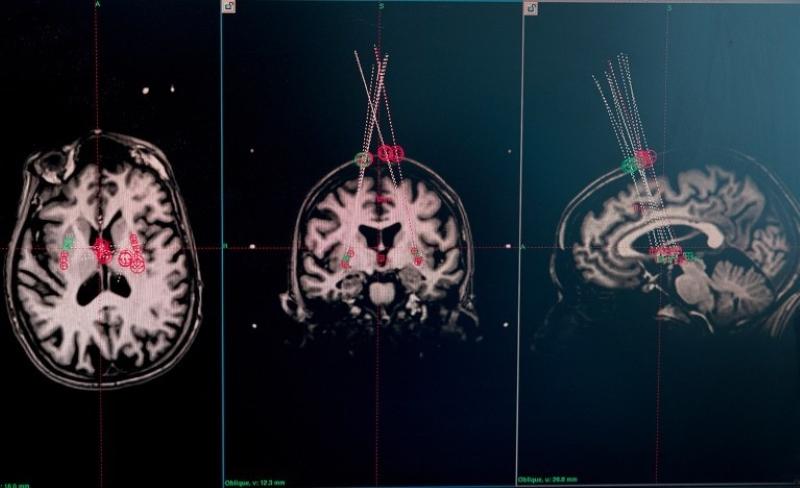

關于癲癇的研究同樣值得關注。在美國神經元治療公司開展的臨床試驗中,外科醫生借助干細胞療法,將干細胞整合到15名癲癇患者的神經回路中。移植一年后,其中兩名參與者嚴重癲癇發作的頻率幾乎降至零,且效果已經持續了兩年。其他大多數參與者的癲癇發作頻率也顯著降低。該公司報告稱,這一療法沒有明顯副作用,也沒有造成認知損傷?;谏鲜鲂Чㄉ窠浽委煿驹趦鹊膱F隊打造的“有效干細胞療法”,也被《麻省理工技術評論》評為2025年“十大突破性技術”之一。